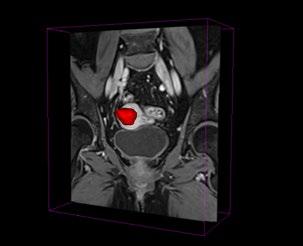

På MMIV1, et forskningssenter ved Radiologisk avdeling på Haukeland Universitetssjukehus, forsker vi blant annet på hvordan kunstig intelligens kan brukes innenfor radiologi. Vi utvikler kunstig intelligens for beslutningsstøtte og forsker på hvordan algoritmene kan gi en mer presis og nøyaktig tolkning av MR-bilder2

Jeg forsker på hvordan vi kan bruke kunstig intelligens til å hente ut mer informasjon fra MR-bilder hos kvinner med livmorkreft.

Livmorkreft er den vanligste formen for gynekologisk kreft blant kvinner i Norge og hvert år får rundt 800 norske kvinner denne diagnosen. Forekomsten av livmorkreft har vært økende de siste tiårene. Før man beslutter behandlingsform tas det vanligvis en MR-undersøkelse av bekkenet for å kartlegge utbredelsen av livmorkreft. De mest avanserte MR-undersøkelsene kan bestå av mange tusen enkeltbilder. Jo mer informasjon man har om svulsten

før man beslutter behandlingsform, desto bedre kan man skreddersy behandlingen til den enkelte og dermed unngå både over- og underbehandling.

En MR-undersøkelse er mer enn bare bilder; den inneholder enorme mengder datainformasjon som er skjult for det menneskelige øyet. Det er derfor avgjørende at vi utvikler verktøy som kan hjelpe oss å hente ut, tolke og benytte oss av all informasjonen som ligger i bildene. Kunstig intelligens kan hjelpe oss med automatisering av tidkrevende arbeidsoppgaver og kan klare å finne mønster i bildene som er utilgjengelig for det menneskelige øyet!

På MMIV har vi utviklet en KI-modell som er et verktøy som automatisk finner en kreftsvulst i livmoren på en MR-undersøkelse hos kvinner med livmorkreft. Når svulsten er lokalisert tegner modellen rundt svulsten i 3D slik at vi får ut et 3D-volum av svulsten som kan brukes til videre analyser. For å få til dette trenger KI-modellen fasitsvar fra radiologer for å kunne lære seg å skille mellom en kreftsvulst og normalt vev på MR-bilder av kvinner med livmorkreft. Som radiolog kan jeg bruke flere timer på å tegne rundt store svulster i alle retninger i 3D og det har man ikke tid til i en klinisk hverdag. For å trene opp en god KI-modell

trengs mange slike 3D-tegninger. Etter opptrening jobber matematikere og dataingeniører med testing av modellen og sjekker hvor bra den er ved å la KI-modellen prøve å se på kreftsvulster den ikke har sett før, det vil si svulster som den ikke har trent på tidligere. Vi har funnet at vår KI-modell kan tegne rundt kreftsvulster i 3D på nivå med radiologer og vi arbeider nå med å tilgjengeliggjøre dette KI-verktøyet i sykehushverdagen på Haukeland. Ved å ta i bruk denne KI-modellen kan man da få en 3D-tegning av en kreftsvulst i løpet av få sekunder i stedet for flere timer og målet er å kunne bruke dette som et klinisk beslutningsstøtteverktøy.

FREMTIDIG BRUK

Det overordnede målet vårt er å kunne bruke kunstig intelligens til å hente ut mer informasjon fra bildene slik at vi kan forstå mer om sykdommen til pasienten. Dette kan være avgjørende for å kunne tilby mer skreddersydd behandling. KI-modellen gir oss også et enormt potensial for videre analyser, vi kan for eksempel avdekke mønster i kreftsvulstene som kan fortelle oss mer om svulstens mikrostruktur. Vi har funnet at mikrostrukturen er veldig forskjellige hos pasienter med aggressiv kreft sammenlignet med

Manuell segmentering. Foto: Privat.

Kontrastforsterket T1-vektet MR bilde av en pasient med livmorkreft der svulsten er visualisert som en 3D-modell. Illustrasjon: Julie Andrea Dybvik og Noeska Smit.

pasienter med mindre aggressiv kreft. Denne informasjonen er viktig fordi det kan hjelpe oss å skreddersy behandlingen bedre til kvinner som får diagnosen livmorkreft i fremtiden. I fremtiden kan vi også tenke oss at vi kan utvikle KI-modeller som verktøy i andre typer medisinske bilder for å forstå enda mer om både livmorkreft og andre sykdommer. Ved MMIV starter vi i år et stort prosjekt3 hvor vi vil utvikle en rekke nye KI-modeller innen radiologi. Algoritmene skal segmentere både normale anatomiske strukturer og patologiske prosesser som svulster, hjerneinfarkt mm. Målet er å skaffe mer objektive og presise målinger for relevante kliniske problemstillinger. Håpet er at dette vil redusere tidsbruk for radiologer samtidig som det bidrar til mer presis diagnostikk.

Det er imidlertid viktig å møte KI med sunn skepsis ved å kontinuerlig evaluere både hva KI kan bidra med, om det er trygt og ikke minst om det er nyttig og gir oss informasjon vi kan stole på. Men ved å gjøre dette kan vi fremme bruken av ansvarlig KI i helsevesenet.